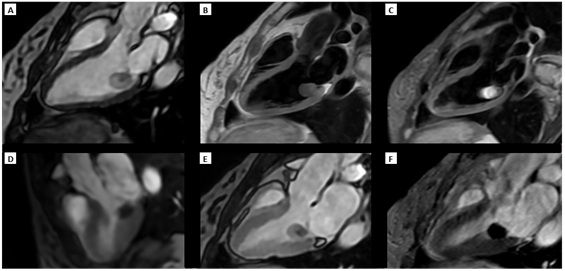

Figure 2. RMC findings: Three-chambers view. A) Cine SSFP sequence: Mass firmly attached to the ventricular surface of segment P1 of the posterior mitral leaflet, cystic in appearance, with mixed content (solid and liquid) and limited mobility. B) FSE T1 sequence: isointense and C) FSE T2 STIR sequence: hyperintense relative to myocardium. D) First-pass gadolinium sequence without perfusion. E) and F) PSIR sequences at early and late gadolinium enhancement respectively without enhancement.